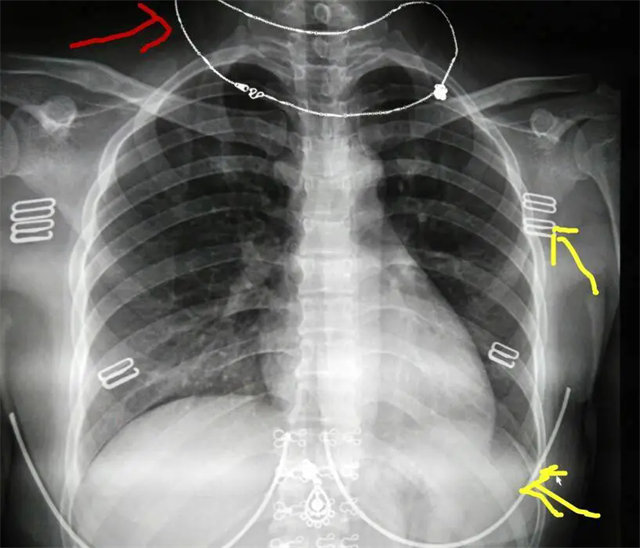

拍攝的不合格胸片的缺陷和解決方法

缺陷:兩肩胛骨未拉開肺野之外,吸氣不完全,且存在金屬飾品遮擋。

解決:去除金屬飾品及內(nèi)衣后重新按標(biāo)準(zhǔn)體位攝片即可。